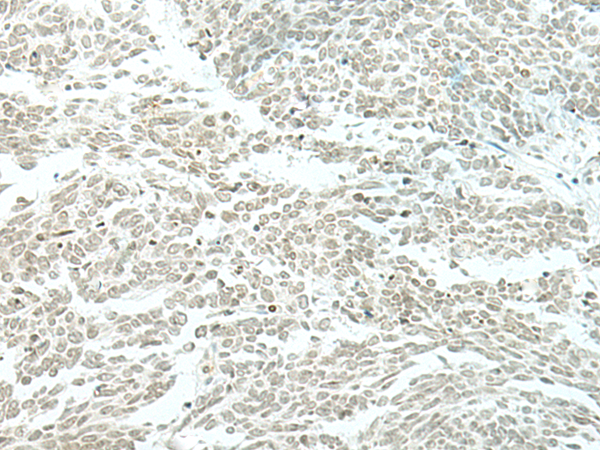

IHC positive control: |

Human lung cancer and Human thyroid cancer |

IHC Recommend dilution: |

30-150 |